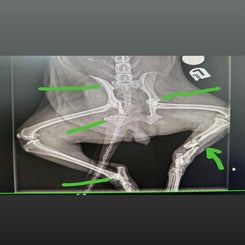

Romina is een oudere hond, met meerdere breuken en een enorme wil om te leven.

Romina heeft onder andere beide achterpoten gebroken, evenals een heup: een verbrijzelde scheenbeenfractuur, een ontwrichte linkerheup, een ontwricht rechter sacro-iliacale os, een schaambeenfractuur en een ischiasfractuur. Vraag niet naar "haar familie", want die is er niet en wordt ook niet verwacht.